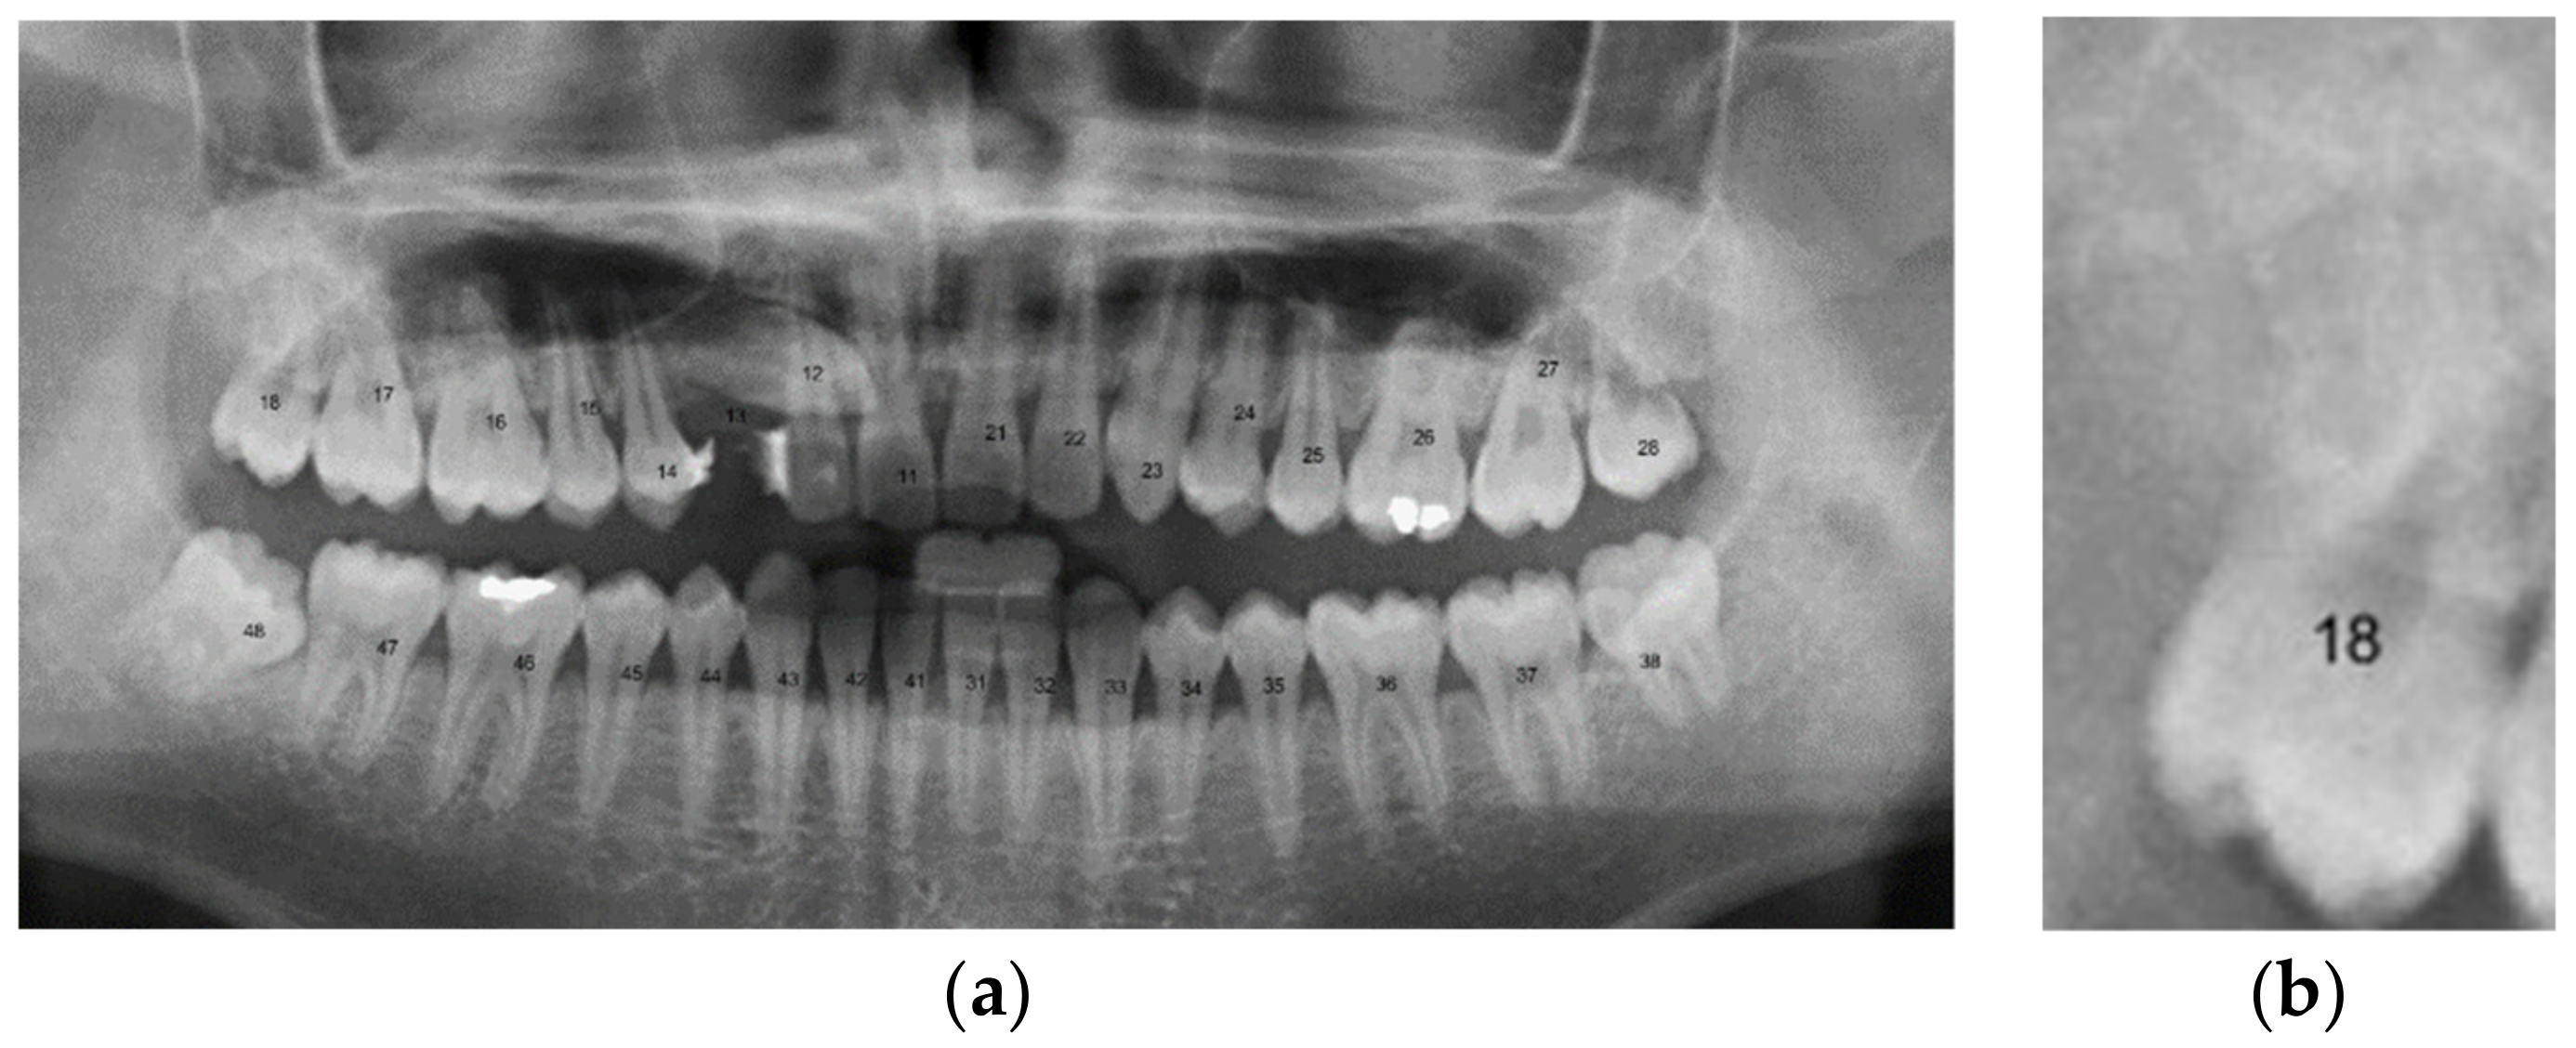

| Tooth Position | [14] | Our Method |

|---|---|---|

| 18 | True | True |

| 17 | True | True |

| 16 | True | True |

| 15 | False | True |

| 14 | False | True |

| 13 | True | True |

| 12 | True | True |

| 11 | True | True |